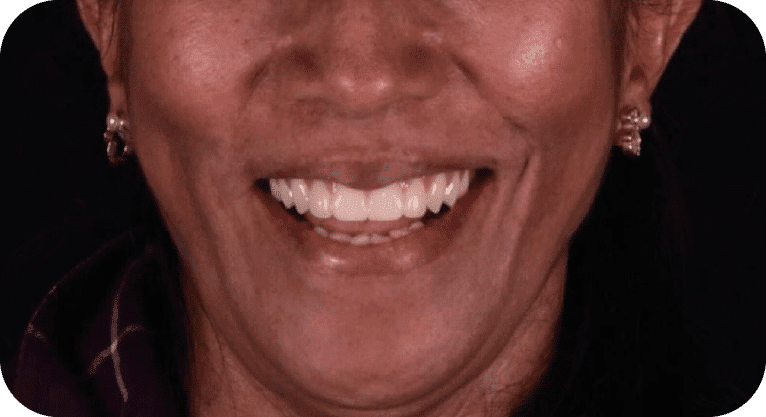

Female patient, “42” years old

Treatment: Dental implant

The patient came to the clinic aer losing two molars due to advanced decay, which affected her chewing function. To restore the edentulous area, dental implants were placed in the corresponding spaces, restoring chewing ability, preventing bone loss, and maintaining the alignment of adjacent teeth, achieving satisfactory functional and aesthetic results.